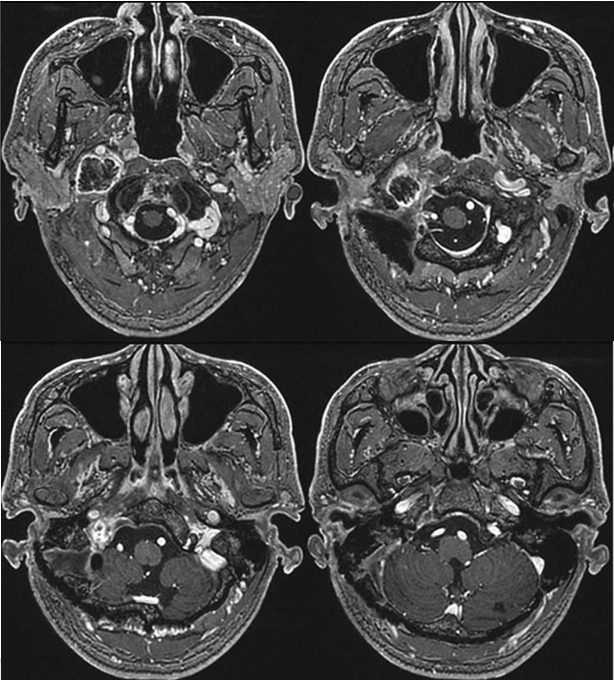

手术需注意避免对肿瘤邻近的后组颅神经和颈内动脉造成解剖损伤。肿瘤完全切除后,颈内静脉的血流得以恢复。术后颅神经功能保留,仅出现轻微功能障碍,随后完全恢复。患者术后未出现新的神经功能缺损,术后磁共振成像证实肿瘤已完全切除。

术后MRI